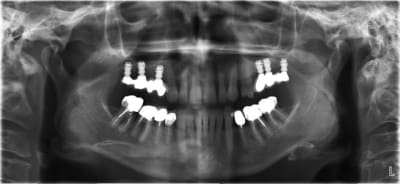

une petite pano pour qu'on se rende compte?

Pour Pluton

voici le cas extraction en décembre 2011 ce qui me pose problème c'est le 2eme implant le 8 mm passe mais le col ne serait pas enfoui , ne vaut il donc pas mieux plus enfouir un 6 mm d'où ma question.

L'os dans le 2 eme site est type 4 et type 3 vers le fond et avec le 8 mm je me retrouve dans la corticale linguale

Mes premiers implants courts: Que des implants courts! Pas assez de recul (2 ans) de plus on voit que celui en 27 n'a pas été enfoui j'ai laissé le col dépassé ( voulait pas qui parte dans le trou trou).

A toi de voir si ça t'aide. Ok je n'avais pas de contrainte d'axe prothétique (grace au système)mais bon ça renseigne un peu.

une petite pano pour une vue d'ensemble?

parce que j'ai l'impression qu'il y a une concavité...donc çà peut être l'indication d'implants pas totalement enfouis + rog pour retrouver une crête sympa...

sinon le deuxième site, moi, me paraît louche...c'est pas du D4, j'aurais plutôt tendance à dire que c'est du tissu de granulation...( et peut être bien un petit morceau de racine...c'est pas très net...)